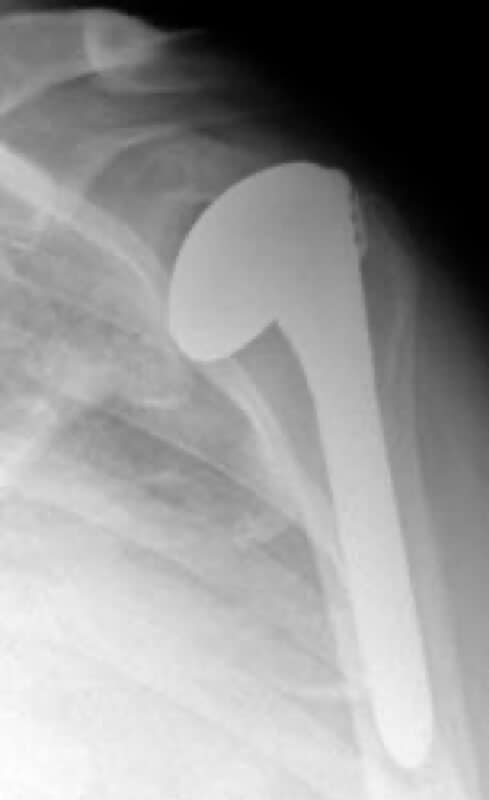

Stryker/Wright/Tornier, Solar Offset